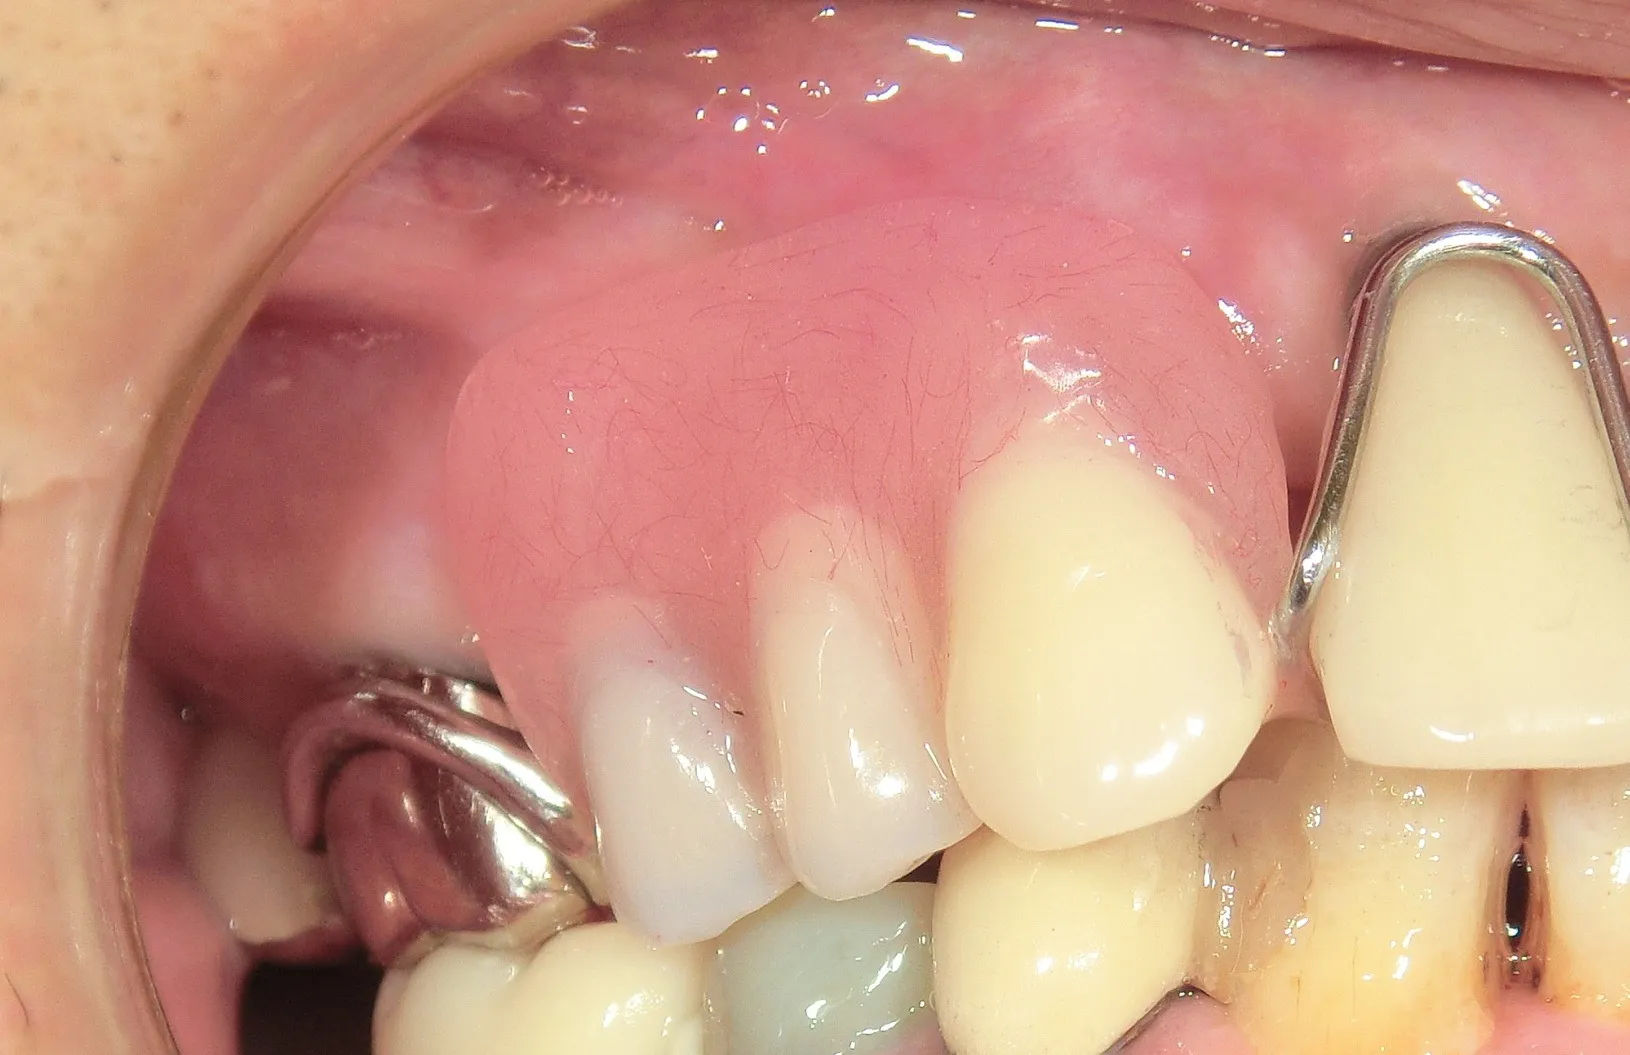

07 インプラント治療

長期的良好経過症例も多い方法を案内

様々なご事情により失った歯の機能と見た目を取り戻すインプラント治療を通して、自然な噛み心地と違和感のない見た目の実現をサポートいたします。30年以上にわたる治療で大多数の症例件数を誇り、歯科用CTによる精密診断と3Dシミュレーションを駆使し、安全で長持ちする治療を提供しております。治療後も定期的なメンテナンスを行い、快適な食生活と口腔の健康を長く守ります。